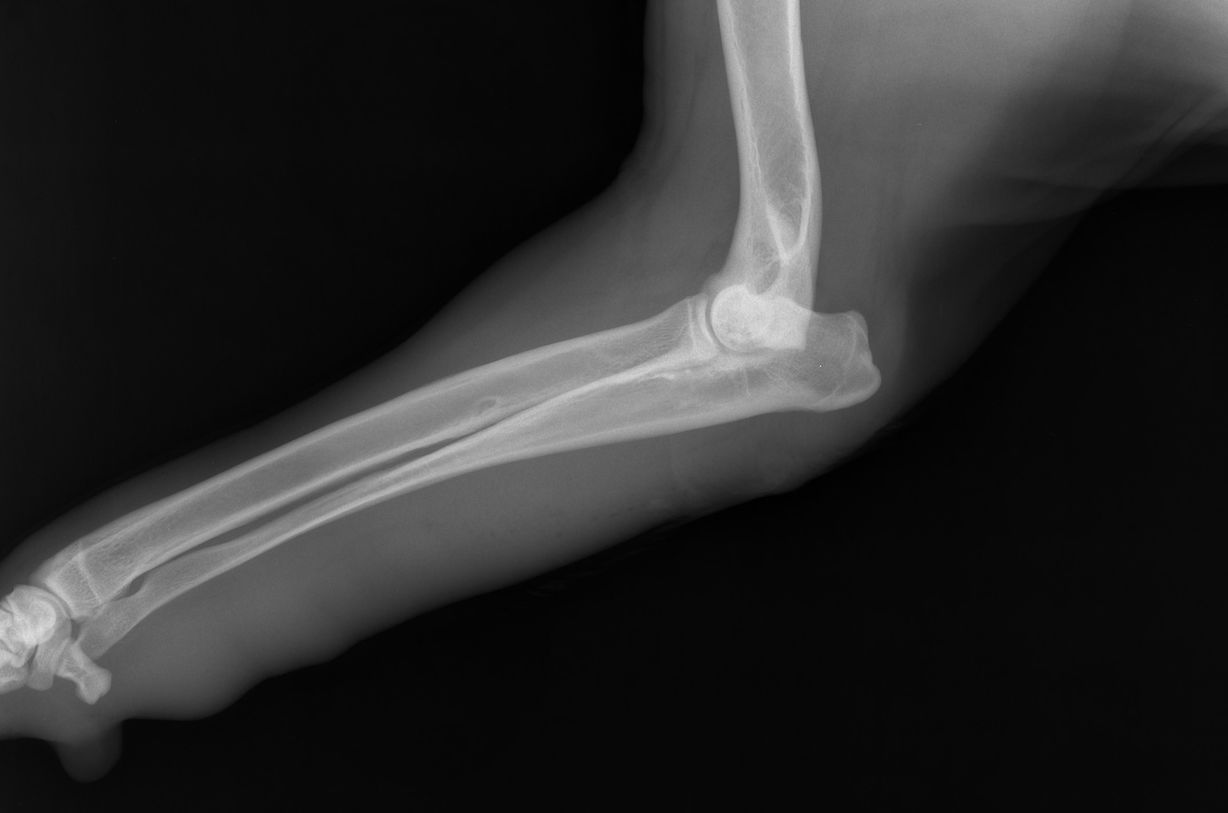

Das Ellbogengelenk wird von den drei Knochen Speiche, Elle und Oberarmknochen gebildet. Um die Beweglichkeit des Gelenks zu gewährleisten, passen diese bei einem gesunden Gelenk perfekt zusammen und verfügen über eine intakte Schicht aus Knorpel.

Passen die Knochen jedoch nicht richtig zusammen, entsteht innerhalb des Gelenks eine übermäßige Reibung. Dadurch nutzen sich im Laufe der Zeit die Knorpel und Knochen ab, was beim betroffenen Hund wiederum zu einer Ellbogengelenkdysplasie und damit zu einer zunehmenden Einschränkung der Beweglichkeit sowie zu Entzündungen und Schmerzen führt.

Ob ein Hund tatsächlich an einer Ellbogendysplasie erkrankt ist, lässt sich letztlich allerdings nur durch Röntgenbilder feststellen. Teilweise kann zusätzlich auch eine Computertomographie (CT) zur Diagnose einer Ellbogengelenkdysplasie erforderlich sein.